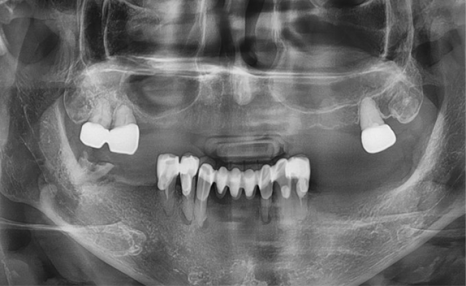

상악동 뼈이식 전 모습 > 상악동 뼈이식 후 모습

상악동 뼈이식 전 엑스레이 > 상악동 뼈이식 후 엑스레이